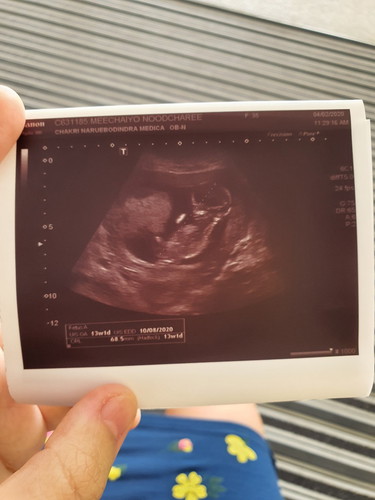

ทำไมเวลาอัลตร้าซาวน์แต่ละครั้ง จำนวนวันตั้งครรภ์ กับวันคลอดจะไม่ตรงกันค่ะ ล่าสุดหมอลงในฟิล์มอัลตร้าซาวน์ว่า13w1d จริงๆควรเป็น13w3d กำหนดคลอดก็เลื่อนไปอีก3วัน เพราะอะไรคะ อันนี้แค่สงสัยว่าในผลอัลตร้าซาวน์คำนวนจากอะไรเป็นหลักคะ

อ่านเพิ่มเติมปกติค่ะ เพราะในใบซาวเลื่อนทุกครั้งเพราะวัดจากขนาดน้อง ครั้งนี้ซาวแม่กินดยอะน้องตัวใหญ่ก็เลื่อนเร็วขึ้น ถ้าเป็นคนปจด.มาสม่ำเสมอใฟ้ยึดกำหนดคลอดตามปจด. ถ้าไม่ให้ยึดตามใบซาวใบแรก แค่ใบแรกใบเดียว ให้ซาวเป็น10ใบก็ไม่ตรงกันหรอกค่ะ อย่างน้อยต้องใช้ความยาวจากหัวถึงเท้า รอบศรีษะ น้ำหนักเป็นเกณฑ์ในการวัดจ้า

ในใบซาวจะเป็นขนาดตัวเด็กที่เจริญเติบโตค่ะวัดเป็นวันและวีคที่คลาดเคลื่อนจากกำหนดจริงได้ถ้าน้องตัวใหญ่หน่อยกำหนดในเครื่องก็จะเคลื่อนไปอีกค่ะเลยทำให้กำหนดคลอดไม่ตรงกันค่ะบ้านนี้ก็เป็นค่ะจาก26+1เป็น26+5ค่ะแต่หมอบอกว่าไม่ต้องกังวลค่ะกำหนดคลอดยังนับจากประจำเดือนตามเดิมค่ะ

ถ้าประจำเดือนคุณแม่แม่นยำก็เอากำหนดประจำเดือนค่ะ ถ้าไม่ตรงก็เอาครั้งแรกที่ซาวด์ เพราะครั้งต่อๆไปที่ซาวด์ กำหนดและอายุครรภ์ไม่แน่นอนเพราะขนาดตัวเด็กด้วยค่ะ เพราะเด็กบางคนใหญ่กว่าเกณฑ์หรือน้อยกว่าเกณฑ์ ไม่เท่ากันค่ะ

มันจะคำนวนจากขนาดมดลูกของเรา และก็ขนาดตัวเด็กค่ะ การอัตตร้าซาวน์คือการคาดคะเนและการพัฒนาการของเด็กค่ะ จะไม่ตรงกันทุกคนค่ะ อย่าเครียดน่ะค่ะ